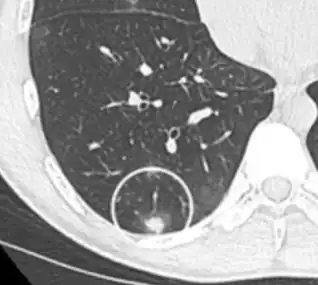

CT image showing centrilobular pattern of GGOs in patient with pulmonary tuberculosis. Note the small, nodular areas of increased attenuation in both lungs.